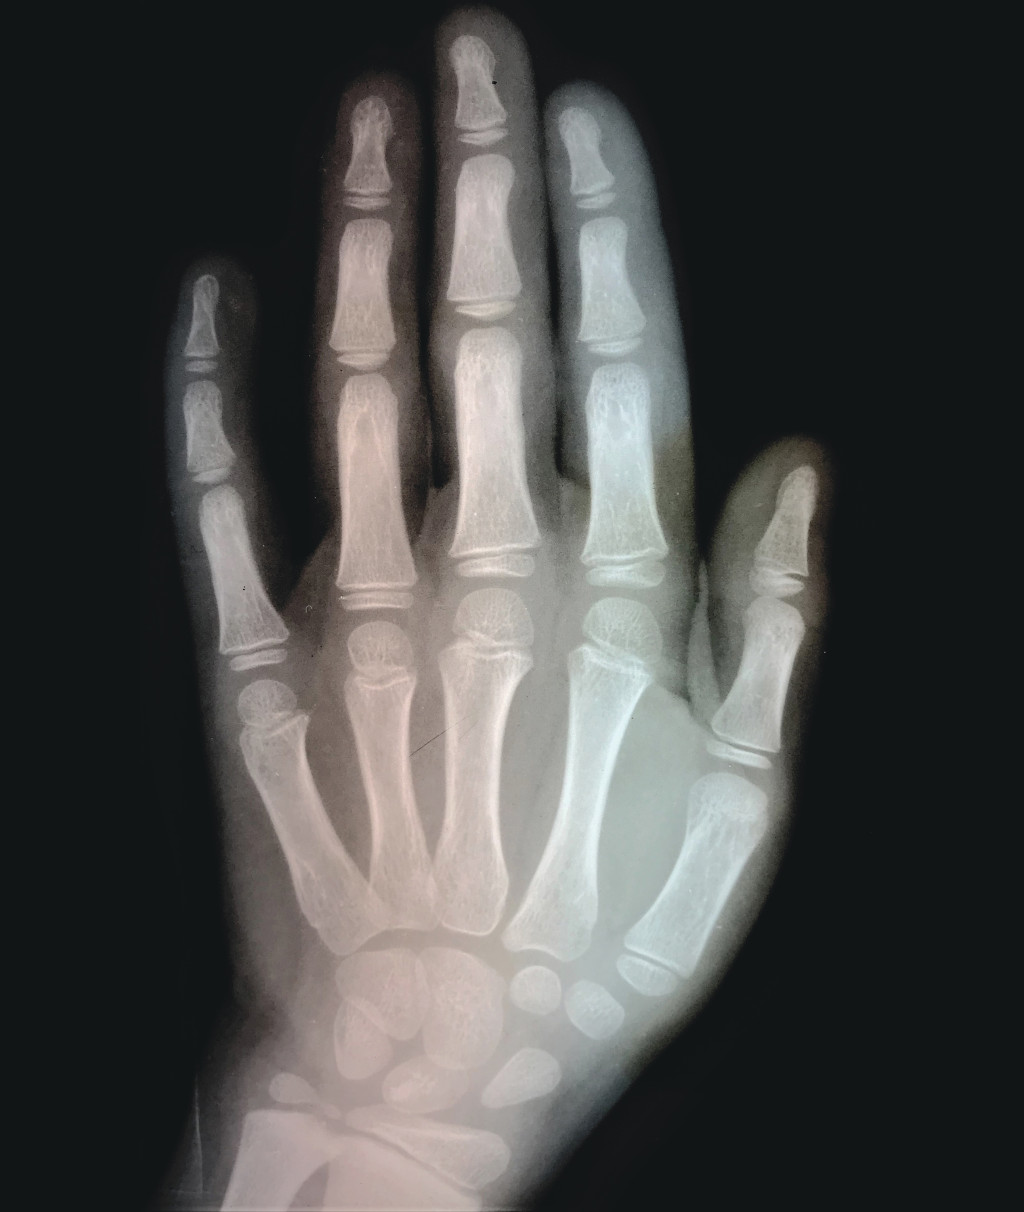

Anatomien lærer oss at tommelen bare har to falanger – en grunnfalang og en ytterfalang – i motsetning til de andre fingrenes tre falanger. Men er det egentlig riktig? Ser vi på et røntgenbilde av en barnehånd, finner vi at falangene bare har én epifyseskive som sitter proksimalt, mens mellomhåndsknoklenes ene epifyseskive sitter distalt. Røntgenbildet avslører imidlertid at tommelfingerens epifyseskiver alle sitter proksimalt (figur 1), både på falangene og på mellomhåndsbenet. Følgelig har den tre falanger som de andre fingrene, men mangler mellomhåndsknokkel. Denne kan gjenfinnes som et rudiment i håndroten hos primatene.

Figur 1 Røntgenbilde av hånden til en niåring. Fra De Schreinerske Samlinger, Universitetet i Oslo.